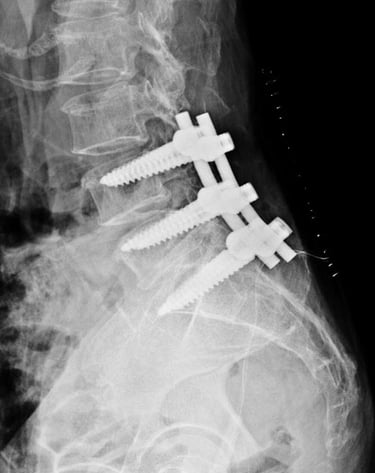

Spine fractures

Expert Surgical/ Non Surgical Care for fractures in the Spine.

Gallery

Explore our advanced spine care visuals.